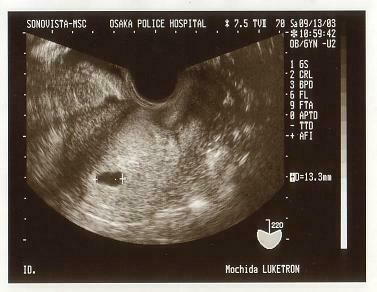

<第一回超音波検査>

9月13日、前日に妊娠検査薬に陽性反応がでたので、家内の

妹の生まれた大阪警察病院に行きます。ちょうど家と会社の間

にあり、通院に便利ということで、この病院に決めました。

超音波検査及び病院での尿検査により妊娠が確定しました。

この時俊介は右の写真の黒い部分、(13.3mm)の袋上の

中にいます。